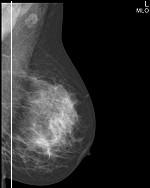

Метод прицельной маммографии с увеличением применяется для более детального исследования определенной области молочной железы. Он отличается высокой точностью диагностики. В отличие от обычной маммографии, которая предоставляет более общую информацию о состоянии молочных желез, прицельная маммография с увеличением позволяет получить точные данные о процессах, происходящих в тканях, благодаря методу компрессии конкретного участка.